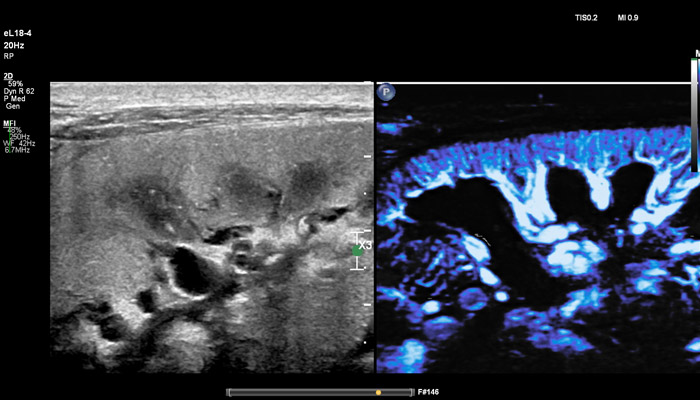

Сочетание усовершенствованной технологии PureWave, комплексного решения по эластографии, высокочувствительной визуализации кровотока (MicroFlow) и точной биопсии представляет собой эффективное решение для ультразвуковой оценки мелких образований.

Рак молочной железы является вторым по распространённости онкологическим заболеванием в мире и составляет около 25% случаев заболеваний среди женщин. Сегодня многие врачи полагаются на ультразвуковую диагностику в выявлении рака у пациенток с уплотнениями ткани молочных желез. При маммографии плотные ткани могут маскировать небольшие раковые поражения. Комплексное исследование молочных желез с применением ультразвукового метода может привести к выявлению еще трех-четырех случаев онкологических заболеваний на 1 тысячу женщин. В распоряжение клиницистов должны попадать решения, которые не только улучшают выявление новообразований и повышают точность диагностики, но также увеличивают пропускную способность кабинета и производительность при сохранении высокого уровня доверия. Линейный матричный датчик eL18-4 используется клиницистами Европы как современное решение для визуализации молочных желез, которое повышает надежность диагностики с помощью таких мощных инструментов, как превосходная визуализация в B-режиме, компрессионная эластография, эластография сдвиговой волной и высокочувствительная визуализация кровотока (MicroFlow Imaging). Кроме того, панорамный режим полезен для оценки распространенности заболевания, выявления большого количества фиброзных изменений и определения расстояния между двумя очагами. Всякий раз, при исследовании молочной железы, превосходное качество изображения и эластография необходимы, чтобы поставить точный диагноз с первого раза и помочь в лечении пациентов.

Накопленный за последние 15 лет клинический опыт показывает, что применение эластографии в дополнение к каждому ультразвуковому обследованию молочной железы приводит к сокращению количества проводимых биопсий, которые раньше проводились в более 80% случаев, но впоследствии оказывались ненужной процедурой".

Линейный матричный датчик eL18-4 поддерживает режим высокочувствительной визуализации кровотока (Philips MicroFlow Imaging), новый запатентованный метод, который обеспечивает инновационный подход к оценке сосудистого русла. Визуализация MicroFlow преодолевает многие барьеры, связанные с традиционными методами обнаружения кровотока в малых сосудах, обеспечивая высокое разрешение при минимальных артефактах. Метод MicroFlow Imaging поддерживает высокую частоту кадров и качество изображения, применяет инновационные методы сокращения артефактов. Варианты вычитания 2D-изображений, смешивания и параллельного отображения обеспечивают превосходную визуализацию в различных клинических случаях.